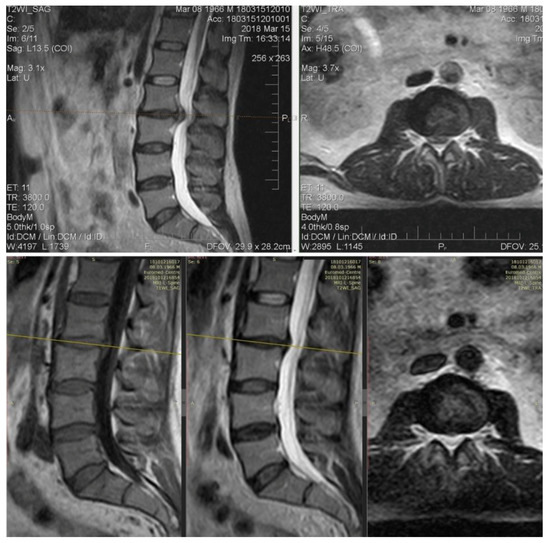

Initial MRI: The extrusion of the intervertebral disk L5–S1 up to 8 mm with stenosis of the foraminal channel is left-sided and compressed by the corresponding structures. With the treatment of dexamethasone, already on day 15 (the first control point), the VAS was 1–2 points, the volume of movements in full. However, neuroimaging for 15 and 30 days does not indicate changes in the intensity of closure plates (type Modic II) or the size of the hernia (Figure 6).

Figure 6. MRI of the lumbar spine images show a large extruded disc fragment at the L5-S1 level. Neuroimaging for 15 and 30 days does not indicate changes of the size of extrusion.